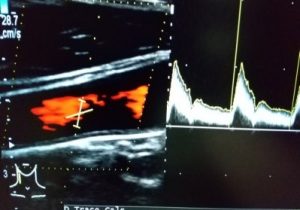

(頸動脈エコープランはスマホで結果閲覧ができませんので検査終了後、医師が結果説明をいたします。)